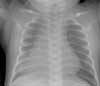

The initial chest radiograph showed a right middle and lower lobe opacity, representing atypical infection, aspiration, or other airspace process (Figure 1). No effusion was seen.

Figure 1